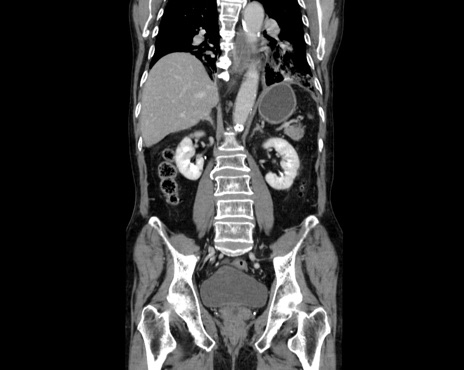

症例26(冠状断像)

横断像

【症例】80歳代男性

【主訴】嘔吐

【現病歴】昨晩2回嘔吐あり、今朝になっても嘔吐あり。来院。

【既往歴】胃潰瘍

【身体所見】意識清明、BT 37.6℃、BP 166/95mmHg、HR 100bpm、SpO2 97%、腹部:平坦・軟、腸蠕動音聴取良好、圧痛なし。

【データ】WBC 21900、CRP 1.4